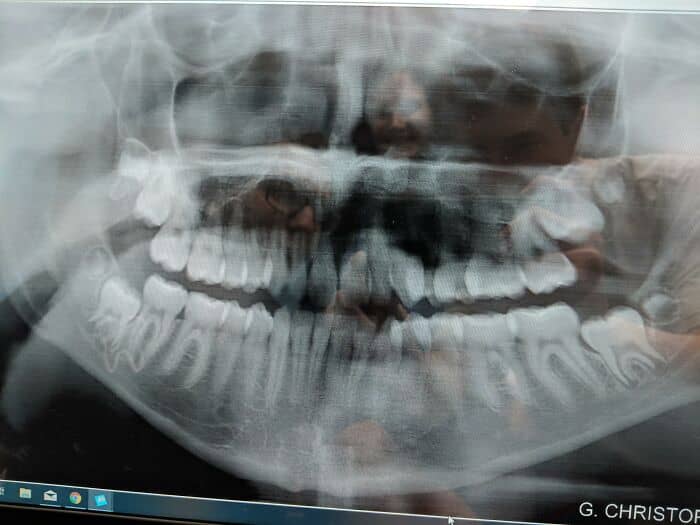

That I had 8 wisdom teeth grow into the extra space in the back of my jaw (two for each side, top and bottom) that all grew in just fine after 20… Only to find out on my last trip to the dentist that I have 8 more growing in sideways…

The normal amount of wisdom teeth is 4. Not 16.